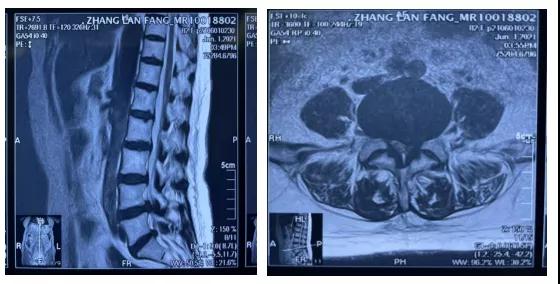

经仔细查体,张奶奶的腰腿痛主要是由于腰4-5椎间盘突出引起。患者年高龄,且基础疾病多,手术难度及风险较大。经过几次详细的综合评估及术前规划、讨论,骨伤二科手术团队为患者实施局部麻醉+静脉复合麻醉的经皮椎间孔镜手术(PELD)手术全程耗时不到半小时,手术切口仅1厘米。微创椎间孔镜技术与传统手术相比,手术时间较短 ,40-50分钟。孔镜下可视下操作,视野清晰更安全,可有效避免误操作的风险,伤口仅为6mm -1cm。术中出血量极少,几乎无出血,患者手术过程中无痛,术后稍痛,术后卧床约 1天左右 ,1天后可基本可自理 ,术后5小时可下地行走,康复时间较快,约(3-6周),复发率低于3%。一般情况下,老年患者的心肺功能通常不太好,过长的手术时间会大大增加手术风险。因此,对手术团队的技术要求较高,必须做到稳、准、快!在尽可能的情况下缩短手术时间,最大程度地减少手术风险。

3.MR:清楚显示突出髓核和硬膜囊、马尾神经、神经根之间的关系 。